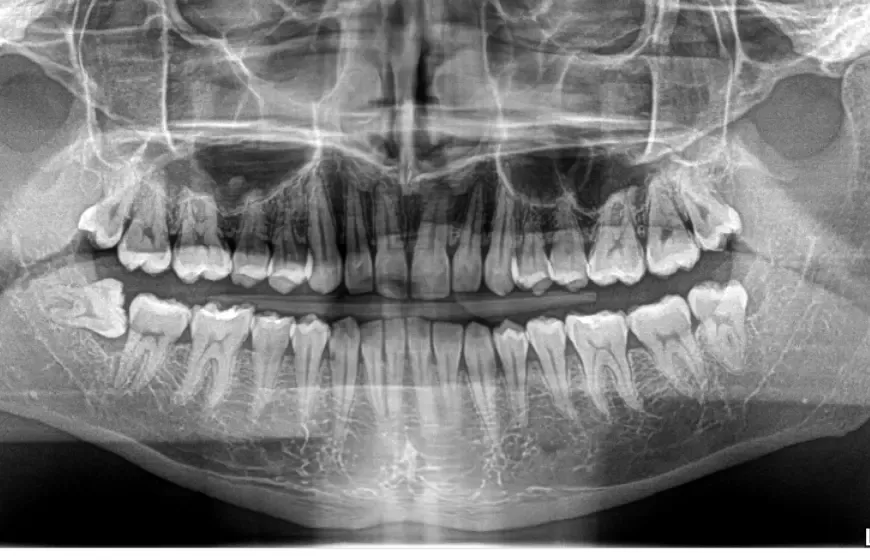

Niewidoczne dla oka, kluczowe dla diagnozy co pokazuje zdjęcie RTG?

Wiele problemów stomatologicznych rozwija się w miejscach niedostępnych dla bezpośredniego oglądania. Dlatego też zdjęcia rentgenowskie czy to pantomograficzne (przeglądowe), czy punktowe (celowane na konkretny ząb) są absolutnie kluczowym elementem diagnostyki. Pozwalają mi zobaczyć to, czego nie widać gołym okiem i postawić trafną diagnozę, która jest podstawą skutecznego leczenia.

Próchnica między zębami: Wróg, którego nie zobaczysz w lustrze

Jednym z największych "niewidzialnych" wrogów jest próchnica na powierzchniach stycznych zębów, czyli tam, gdzie zęby stykają się ze sobą. Tego typu ubytki są niewidoczne podczas standardowego badania, nawet przy użyciu kamery wewnątrzustnej. Zdjęcia RTG są tutaj niezastąpione wyraźnie pokazują ciemne plamy między zębami, świadczące o rozwijającej się próchnicy. To dlatego tak często zalecam wykonywanie zdjęć rentgenowskich co jakiś czas.

Korzenie pod kontrolą: Ocena stanu zapalnego i leczenia kanałowego

Zdjęcia RTG są również niezbędne do oceny stanu korzeni zębów oraz tkanek okołowierzchołkowych. Dzięki nim mogę sprawdzić, czy nie ma tam zmian zapalnych, torbieli czy ubytków kostnych. Są one również kluczowe podczas monitorowania efektywności leczenia kanałowego pozwalają mi ocenić, czy wypełnienie kanałów jest szczelne i czy stan zapalny został wyleczony. Bez RTG leczenie endodontyczne byłoby jak poruszanie się we mgle.

Zatrzymane ósemki i inne anomalie: Co kryje się w twojej szczęce?

Wiele problemów rozwojowych i anomalii w strukturze szczęki jest całkowicie ukrytych. Zdjęcia rentgenowskie pozwalają mi zdiagnozować zęby zatrzymane (najczęściej ósemki, które nie mają miejsca na wyrznięcie się), ocenić ich położenie i potencjalny wpływ na sąsiednie zęby. Mogę również wykryć torbiele, zanik kości, obecność dodatkowych zębów czy inne nieprawidłowości, które mogłyby w przyszłości prowadzić do poważnych komplikacji.